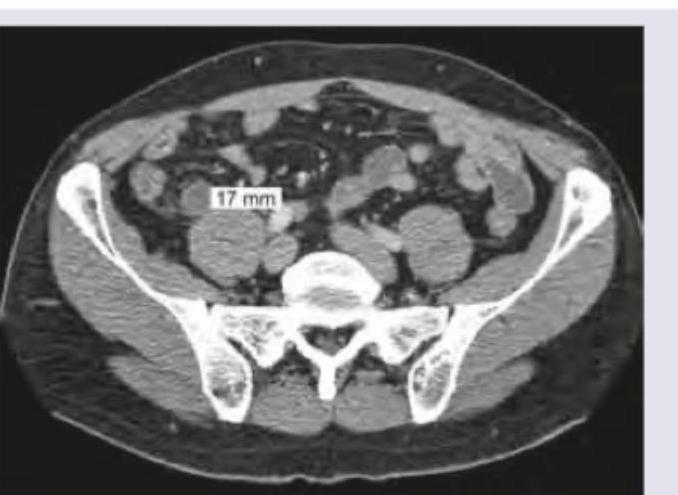

Explanation: ***Acute appendicitis*** - The CT scan shows a dilated, **thickened appendix** measuring 17 mm in diameter, which is a classic finding for acute appendicitis. - The patient's presentation with acute right lower abdominal pain is highly consistent with this diagnosis. *Acute salpingo-oophoritis* - This condition involves inflammation of the **fallopian tubes and ovaries** due to infection, typically causing bilateral lower abdominal pain and fever. - The image does not show findings specific to salpingo-oophoritis, such as **tubo-ovarian abscess** or significant adnexal inflammation. *Ruptured ectopic pregnancy* - A ruptured ectopic pregnancy would typically present with severe lower abdominal pain, **vaginal bleeding**, and hemodynamic instability in a female patient, none of which are described. - Imaging would typically show **pelvic free fluid** and an adnexal mass, rather than an inflamed appendix. *Intestinal obstruction due to Meckel's diverticulum* - Intestinal obstruction would present with **abdominal distension**, vomiting, and changes in bowel habits, which are not mentioned in the patient's presentation. - While Meckel's diverticulum can cause obstruction, the primary finding on this CT is a **dilated appendix**, not bowel obstruction.